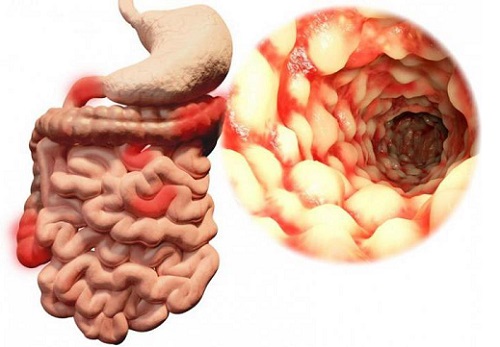

С точки зрения тканевых изменений в слизистой оболочке илеита наблюдаются классические признаки воспаления – покраснение, отечность тканей, повышение местной температуры, болезненность, которая манифестируется болями в животе, ухудшение всасывающей способности подвздошной кишки.

Илеит – острое или хроническое воспалительное поражение подвздошной кишки, которая является конечным отделом тонкого кишечника.